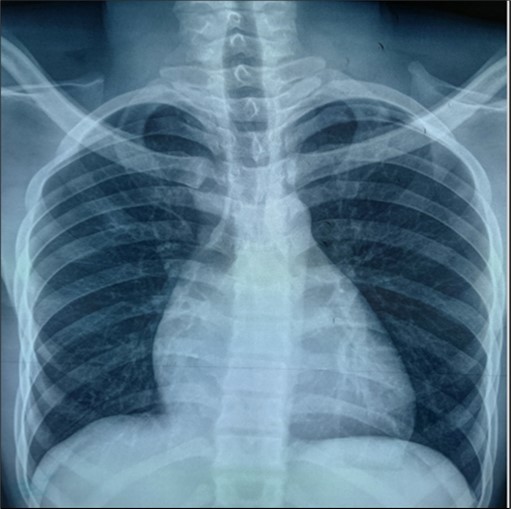

The frontal chest X-ray showed cardiomegaly with a cardiothoracic index of 0.7. The thoracic cavity and pulmonary parenchyma were without abnormality (Figure 1).

Figure 1.Frontal chest radiograph showing cardiomegaly

Frontal chest radiograph showing cardiomegaly

Cardiomegaly is frequent in Ebstein’s anomaly. A cardiothoracic ratio of at least 0.65 is associated with a poor prognosis 8 . This was the case with our patient.